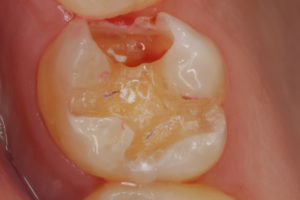

2枚目は金属を外したところです。案の定至る所に汚れや虫歯が見られます。黒いのは、細菌の固まりです。